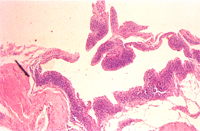

關節: (1) 滑液囊絨毛上皮細胞增生,絨毛之皮下組織可見多數單核細胞浸潤、呈淋巴濾泡樣排列(圖4)。